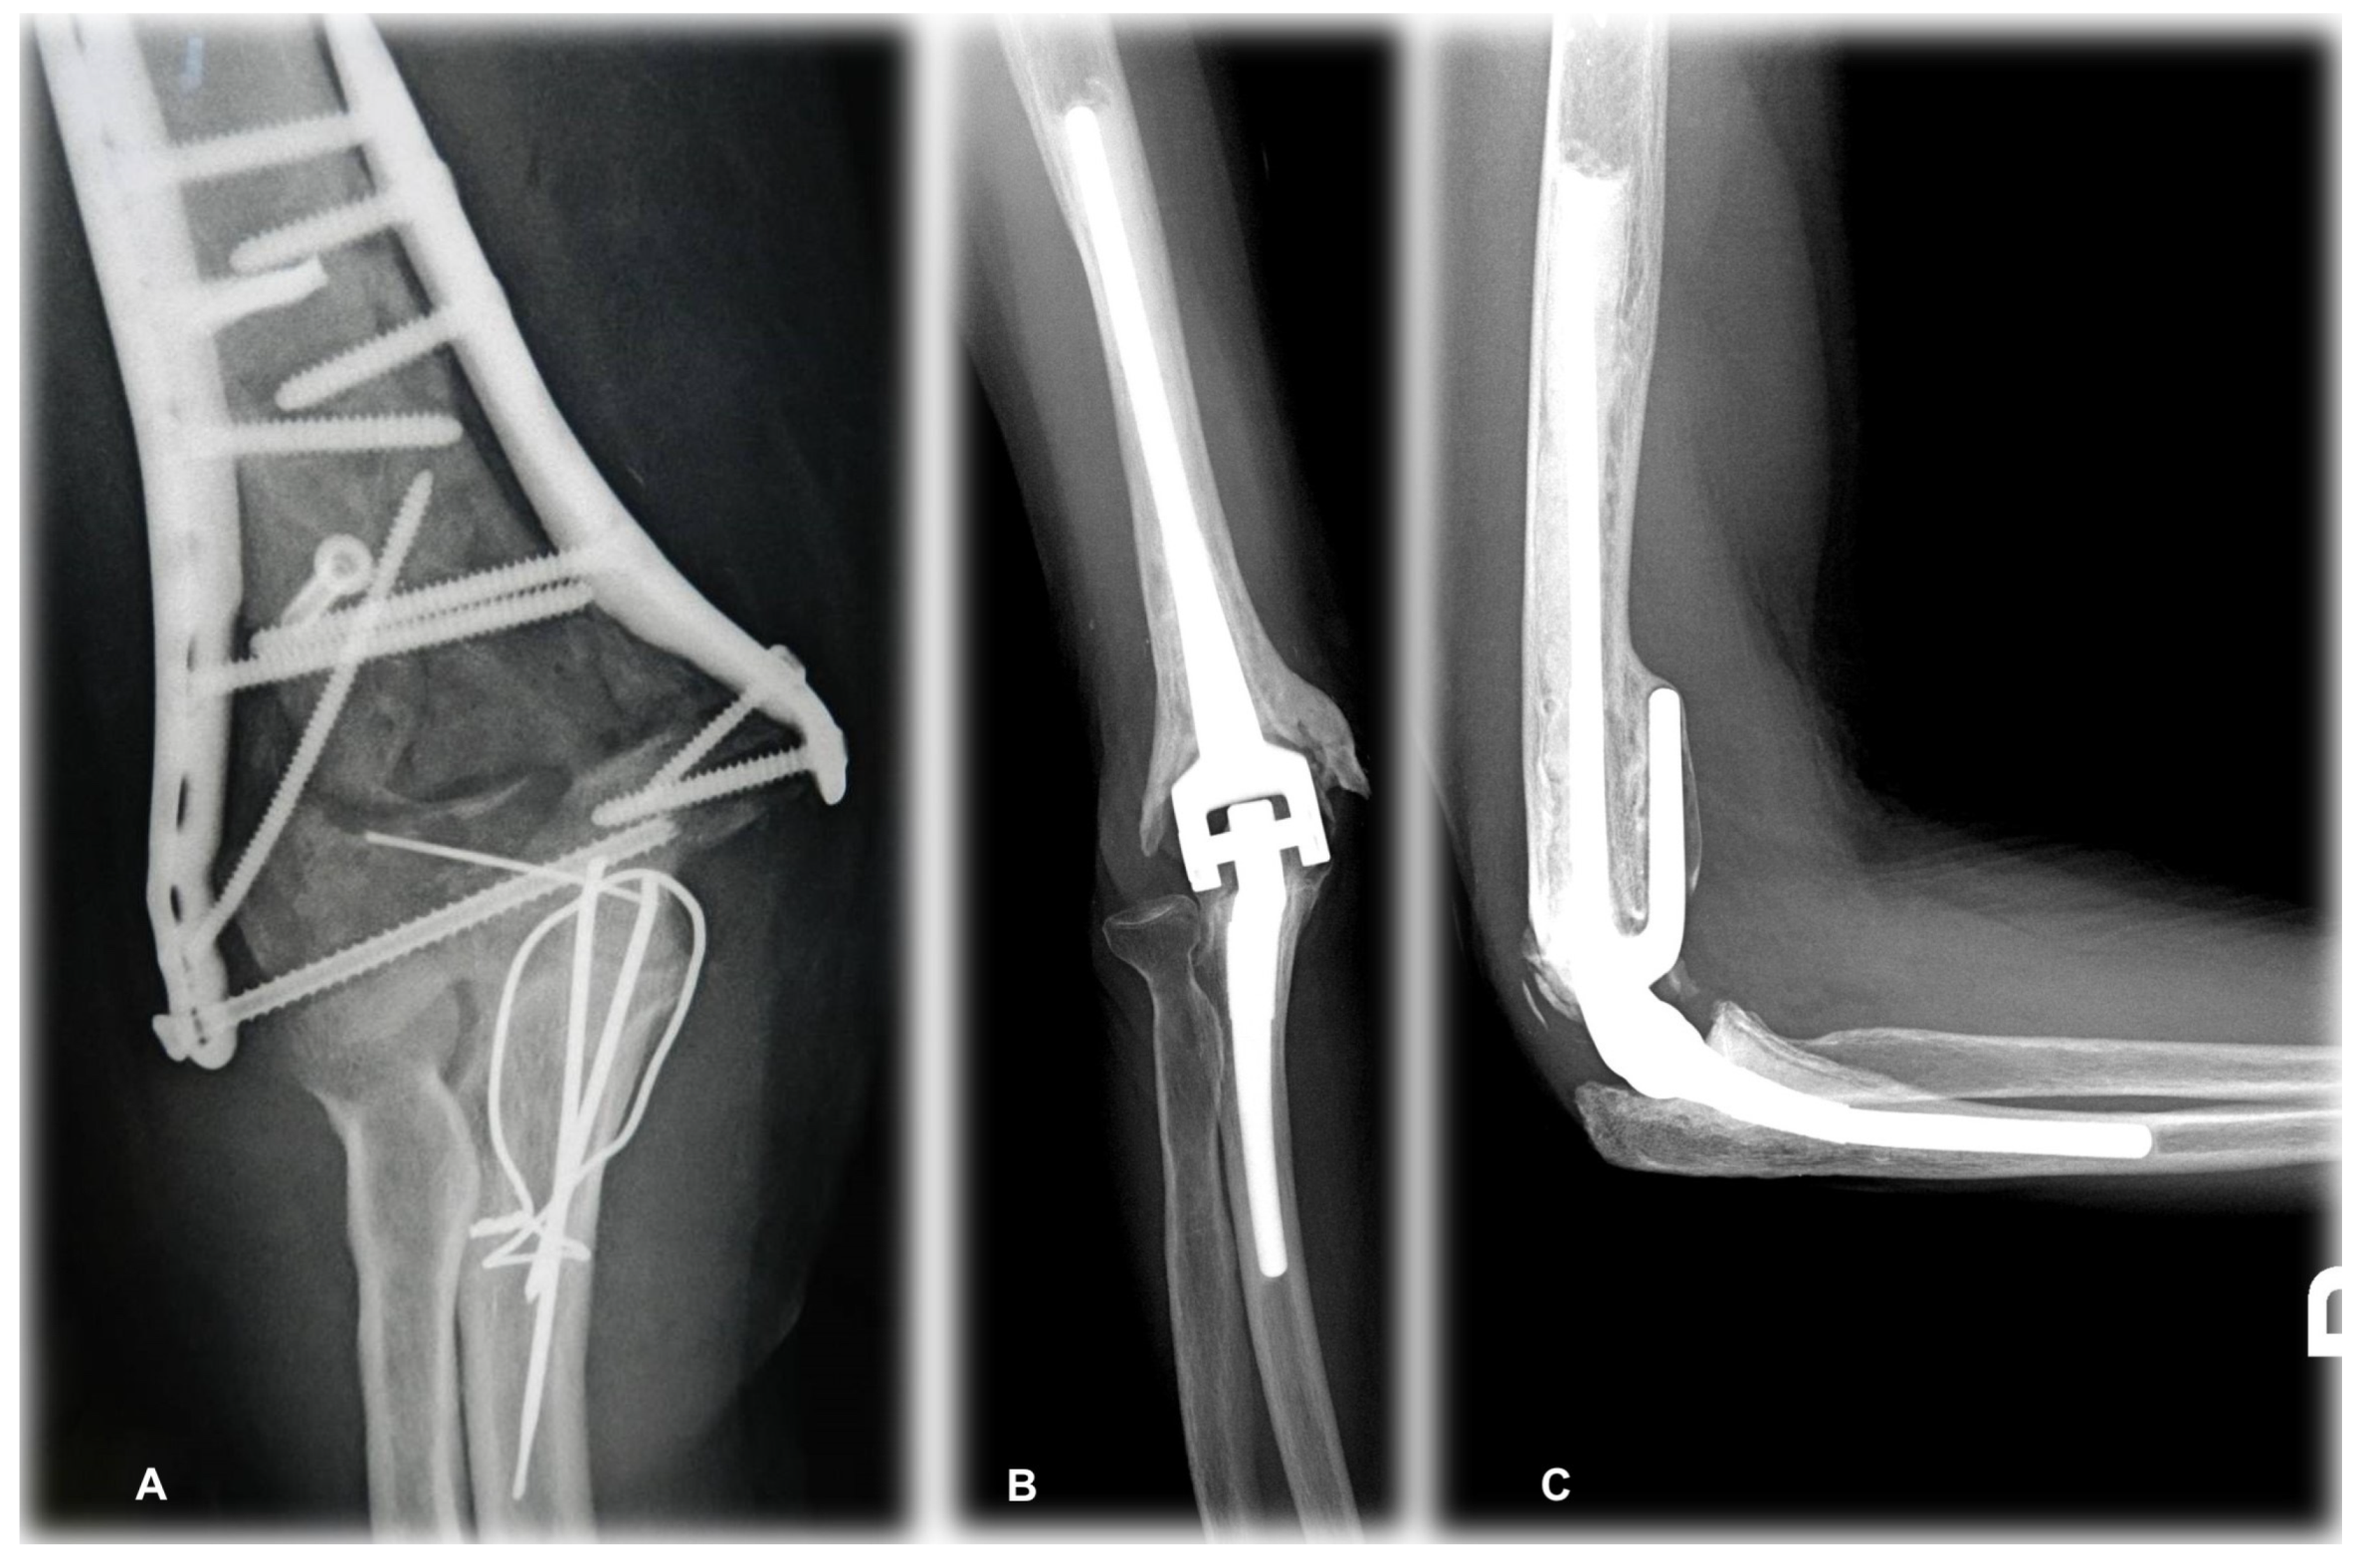

2. Materials and Methods

3.2. Radiographic Outcomes